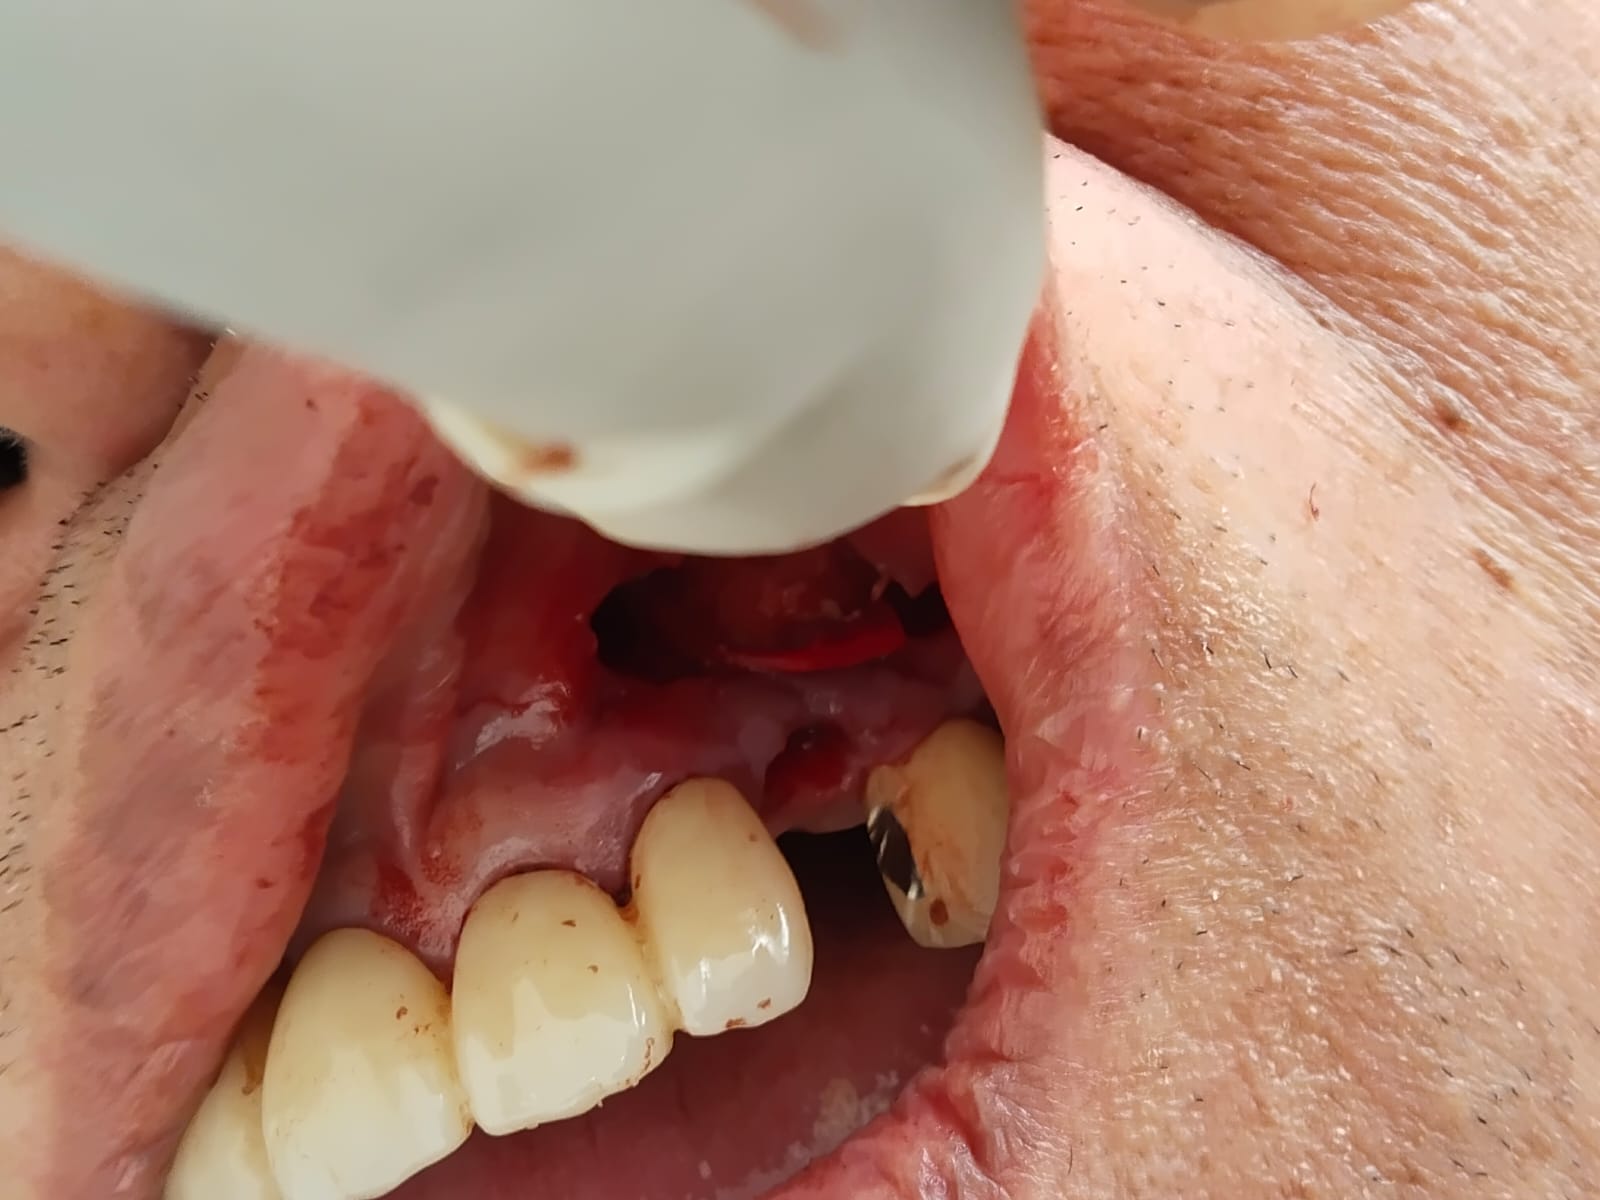

The procedure is usually done under local anesthesia or sedation, depending on the case. Recovery time varies, but most patients can return to normal activities within a few days. After the extraction, it’s important to follow your dentist’s aftercare instructions, such as keeping the area clean, managing swelling with ice packs, and avoiding certain foods temporarily. Wisdom tooth extraction can help prevent future dental issues, relieving pain and supporting overall oral health. You may visit our practice and meet Dr Rahman who is well trained for dental surgical procedures and best doctor for wisdom tooth extraction in Dhaka

Local anesthesia or sedation is used, so there’s minimal discomfort during the procedure. Some soreness is expected afterward, which can be managed with pain relievers.